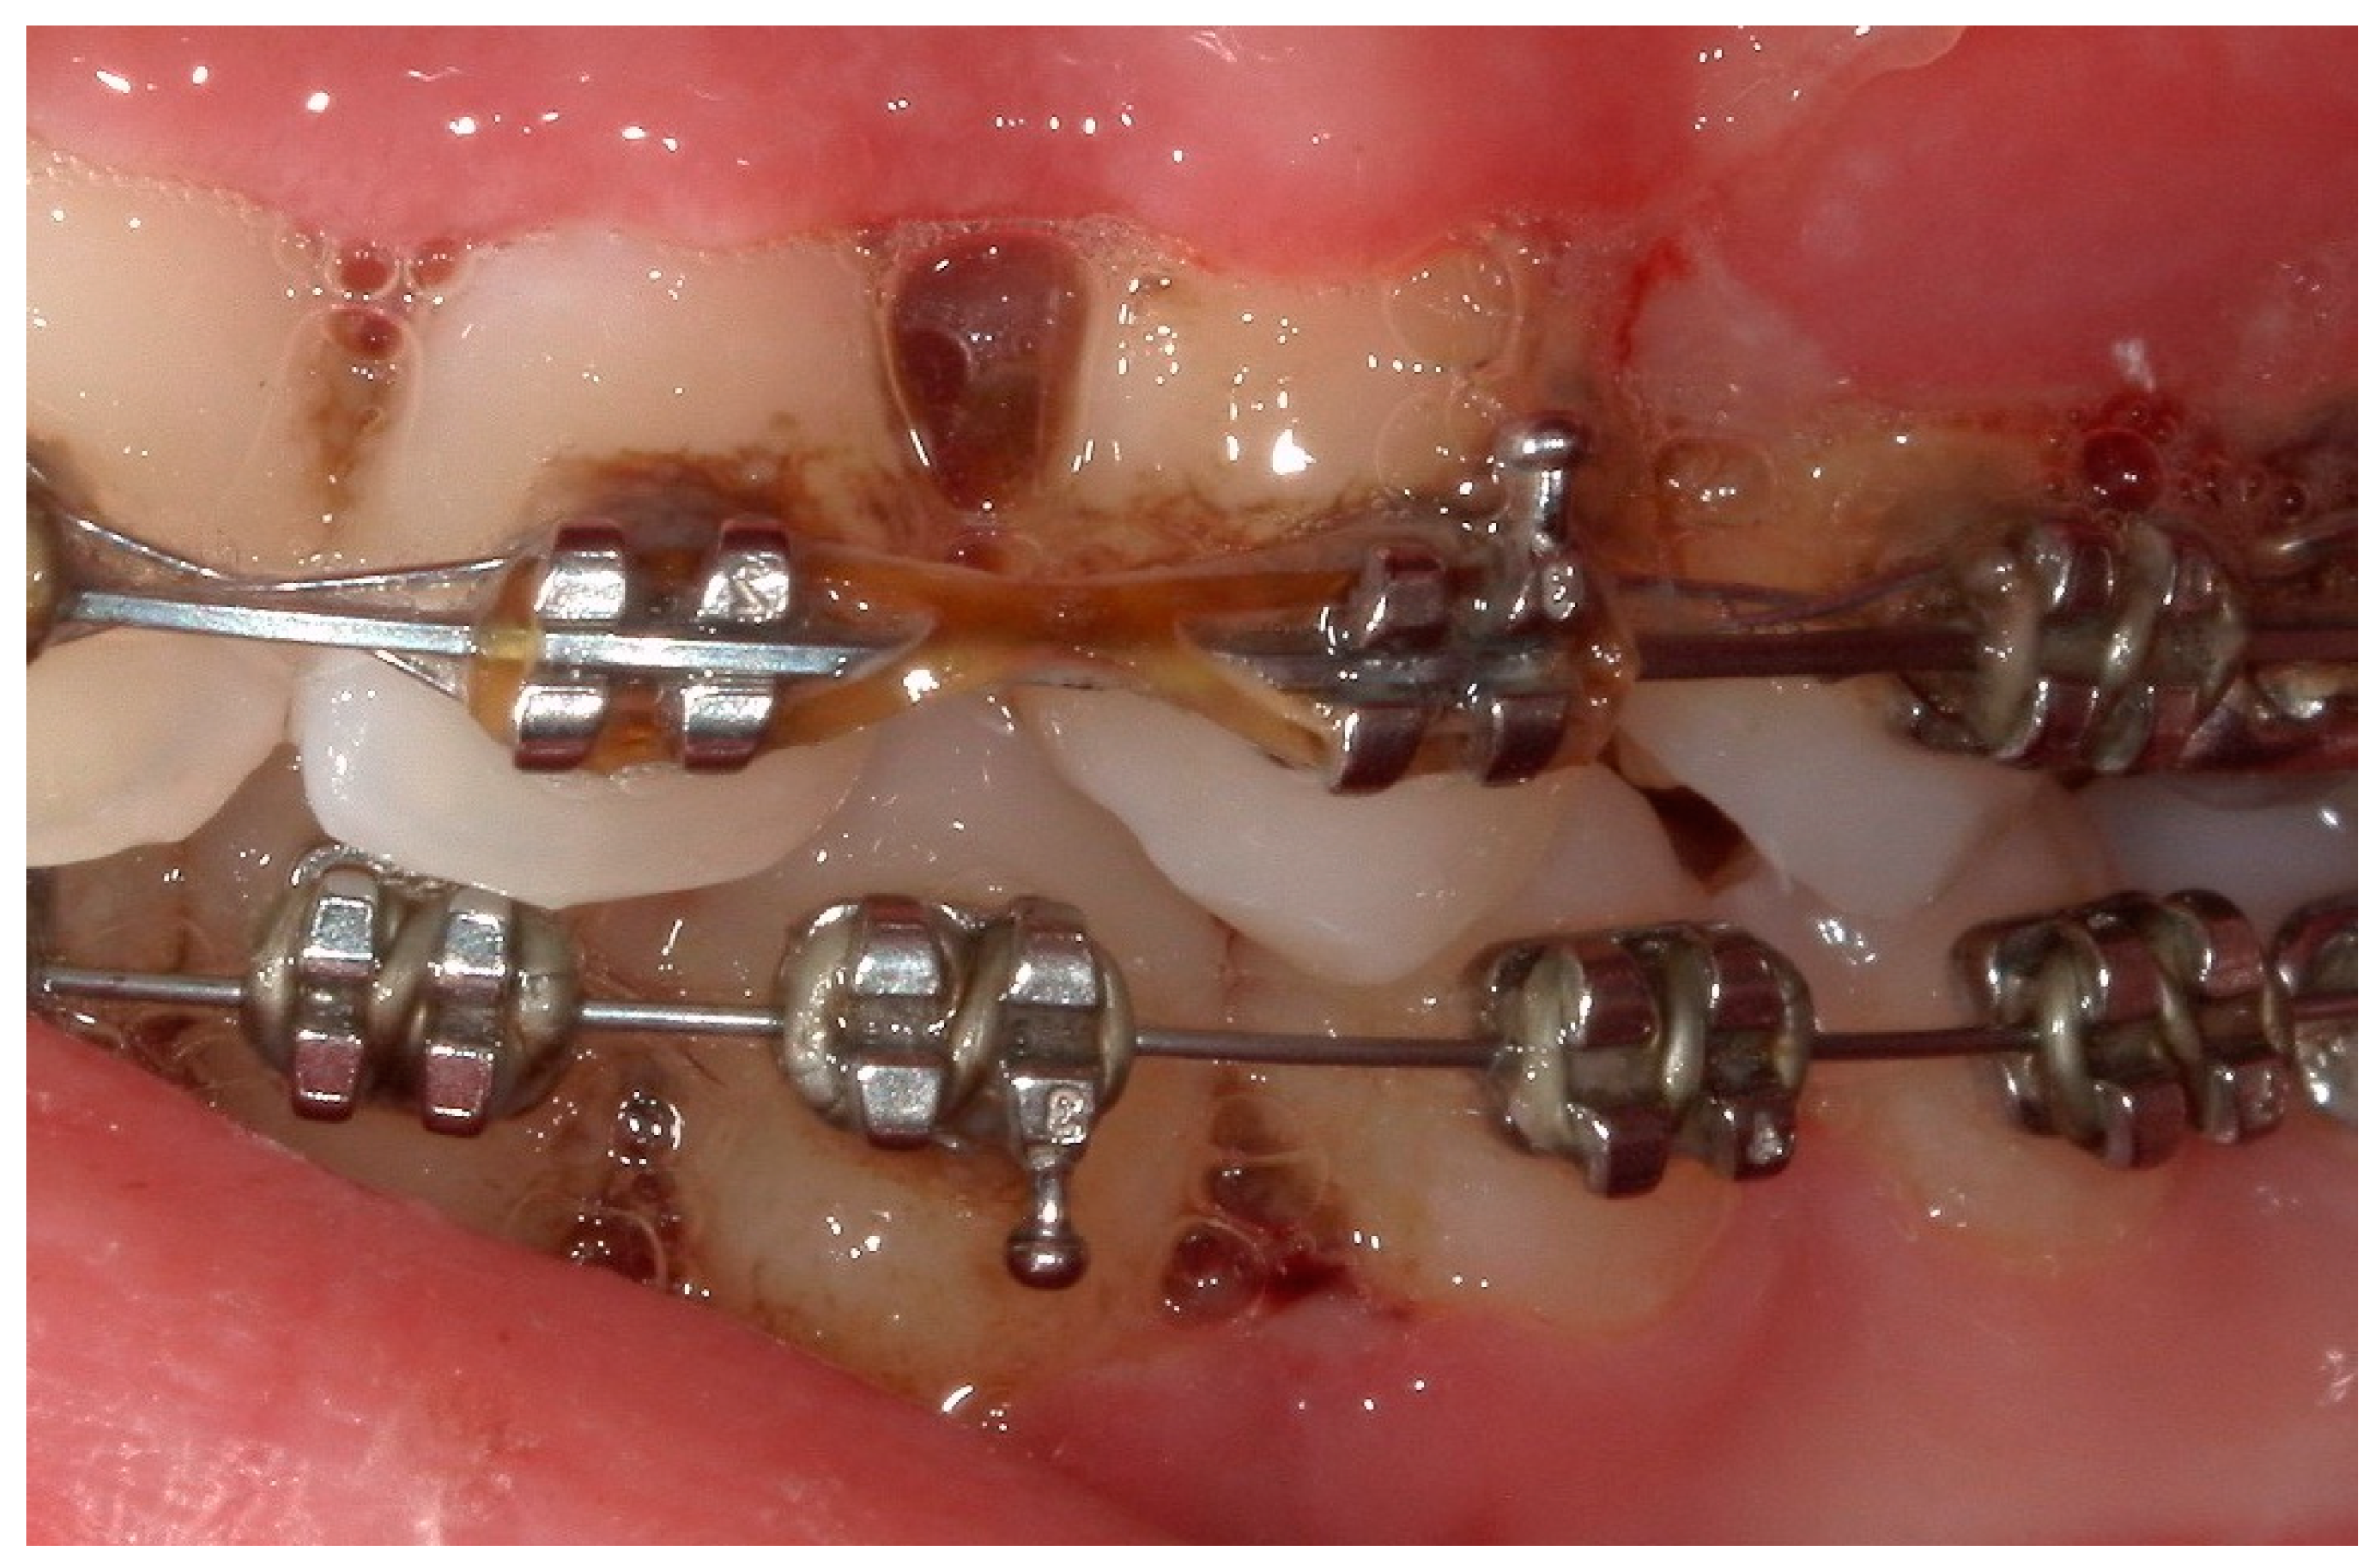

4.2. Case 2